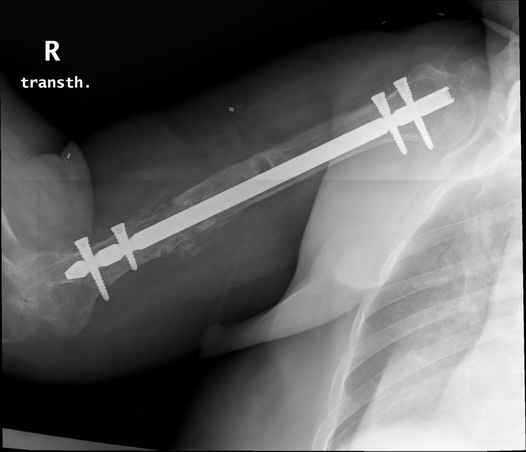

Больная 48 лет, медсестра-массажист, перелом плеча 7 лет назад, оперирована 4-кратно и безуспешно

Больная 48 лет, медсестра. Травма получена 7 лет назад, оперирована первично в Турции - остеосинтез пластиной - несращение - реостеосинтез стержнем там же через год (обычным, с выстоянеием его в полость плеча) - несращение - поступила к нам впервые в марте 2008 года - удаление стержня, реостеосинтез пластиной и костная пластика, в течение 2 лет лизис кости вокруг винтов, смещение фиксатора, в марте 2010 - удаление пластины, реостеосинтез интрамедуллярным стержнем с блокированием (рассверливание + костная пластика). В динамике - вновь лизис в области перелома, нестабильность дистальных блокирующих винтов.